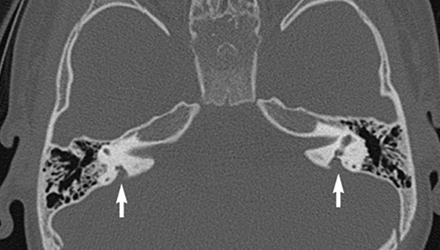

SLC26A4基因--大前庭導(dǎo)水管相關(guān)致聾基因

SLC26A4基因定位于人類染色體7q31,SLC26A4基因和大前庭導(dǎo)水管綜合征相關(guān)突變位點的發(fā)現(xiàn),證實SLC26A4是大前庭導(dǎo)水管綜合征的責(zé)任基因。

我們平時提到的“一巴掌打聾”、“一跤摔聾”其實都與SLC26A4基因突變有關(guān),絕大多數(shù)大前庭導(dǎo)水管綜合征都是SLC26A4基因突變?nèi)堑牡湣?/p>

SLC26A4基因編碼一種叫“Pendrin”的跨膜轉(zhuǎn)運蛋白,在機體離子成分平衡的維持中發(fā)揮重要作用。

在內(nèi)耳,Pendrin表達(dá)于內(nèi)淋巴管、內(nèi)淋巴囊、橢圓囊、球囊等處,異變的蛋白將對這些結(jié)構(gòu)的正常生理功能產(chǎn)生影響,引發(fā)聽損。

SLC26A4基因突變導(dǎo)致的大前庭導(dǎo)水管綜合征的典型表現(xiàn)為兒童時期的聽力損失,90%的患者為雙側(cè)性,聽力損失程度不一,可表現(xiàn)為接近正常或重-極重度。

病程可為穩(wěn)定性、進行性或波動性,聽力可逐步下降至全聾;跌倒、撞擊等行為或無外界影響都可能引發(fā)聽力的下降。